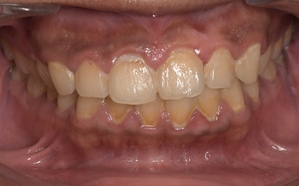

中等度歯周病

特徴

歯肉炎~歯周炎の段階です。

• 腫れや歯磨きの時の出血が頻繁に起こる

• 歯はグラつかない、もしくは少しグラつく

• 口臭がある

• 歯ぐきがムズムズする感じがある

• 歯周ポケットが深くなる

• 歯の周囲組織の破壊が始まる

中等度歯周病の歯ぐきの写真

治療内容

歯科医院で深くなってしまった歯ぐきの溝の中にある汚れを専用の器具で除去する必要があります。溶けてしまった骨は一般的には元通りに戻りません。歯ブラシの毛先を当てて磨くことで一時的に症状が治まることがあります。歯周病は慢性的に進行することが多く中程度歯周病の場合、進行を防ぐため歯科医院と相談しながら定期的にクリーニングを受けるようにしましょう。